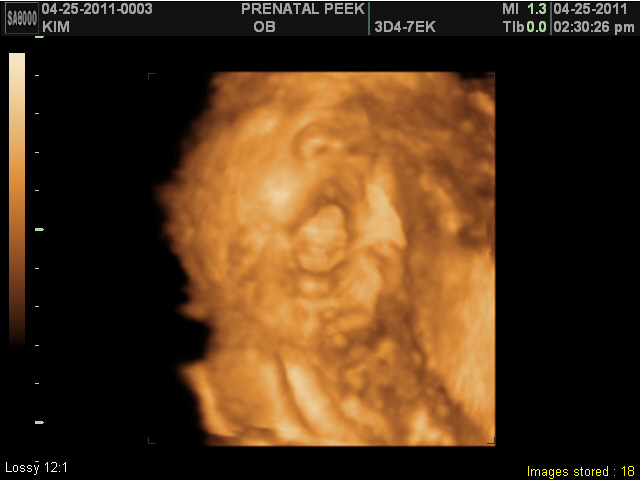

Prenatal Peak Round 2